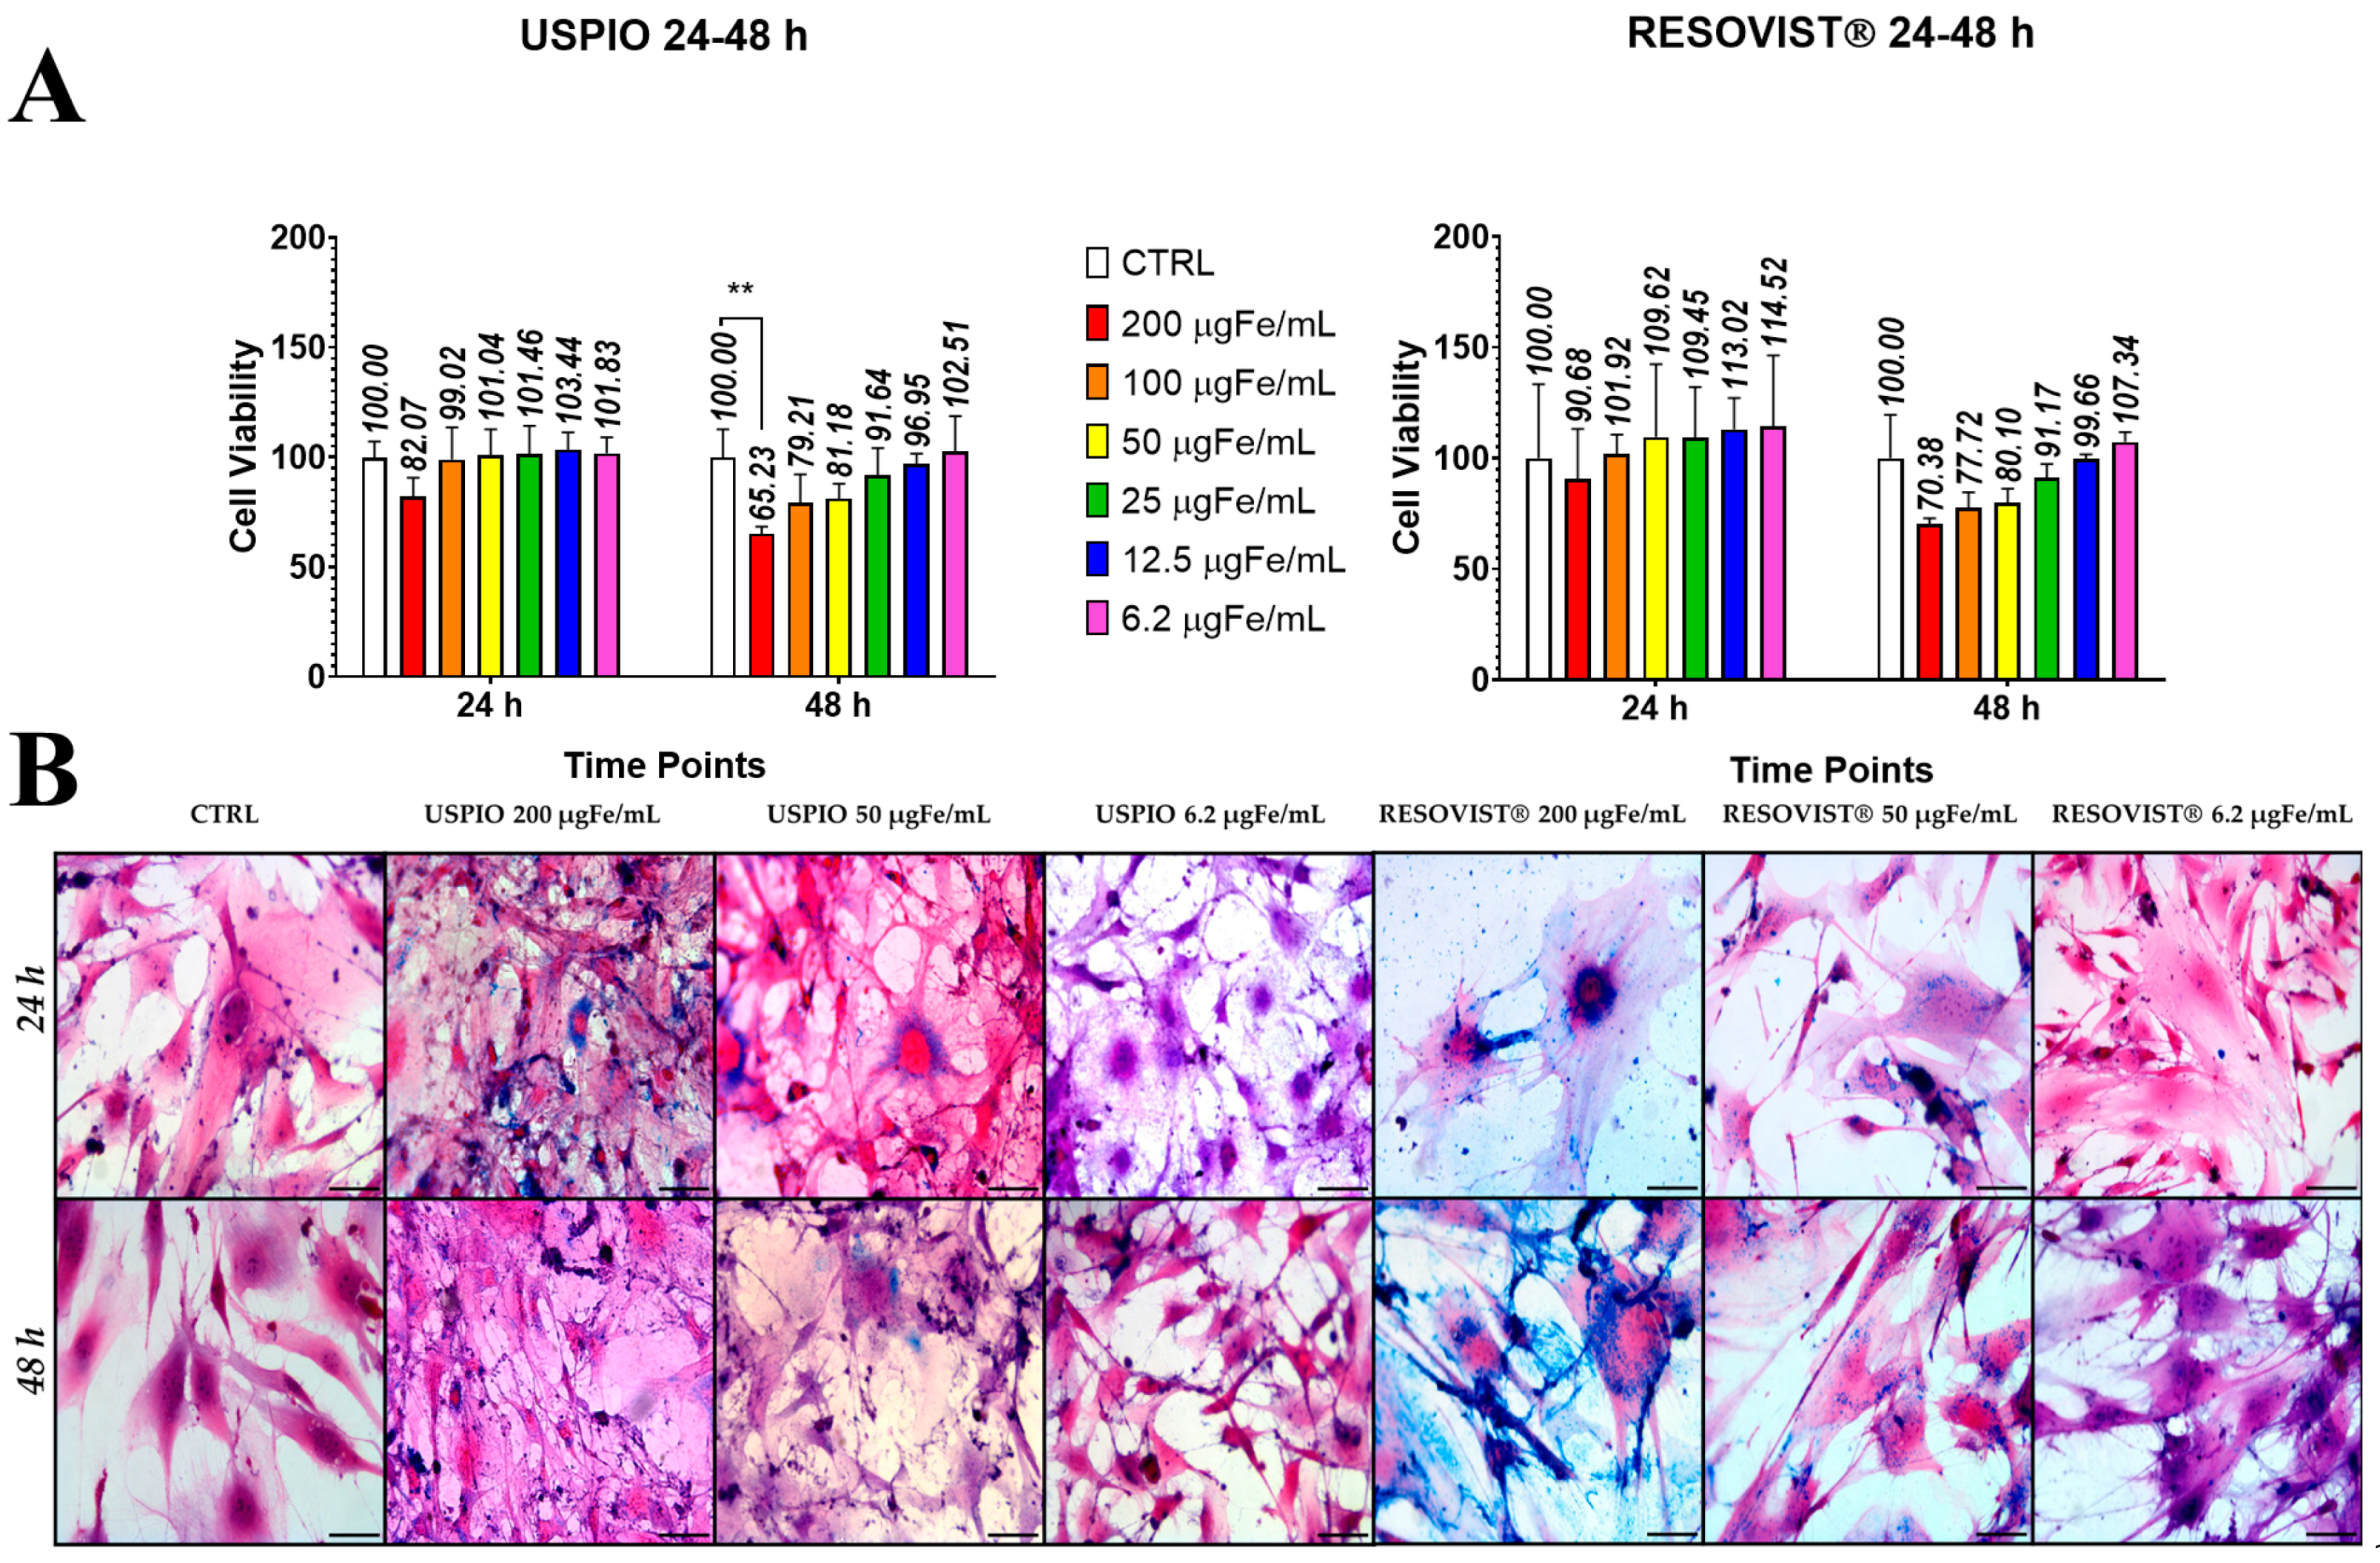

2.2. Toxicity and Internalization of NPs in ADAS

4.2. Internalization of Nanoparticles into Stem Cells